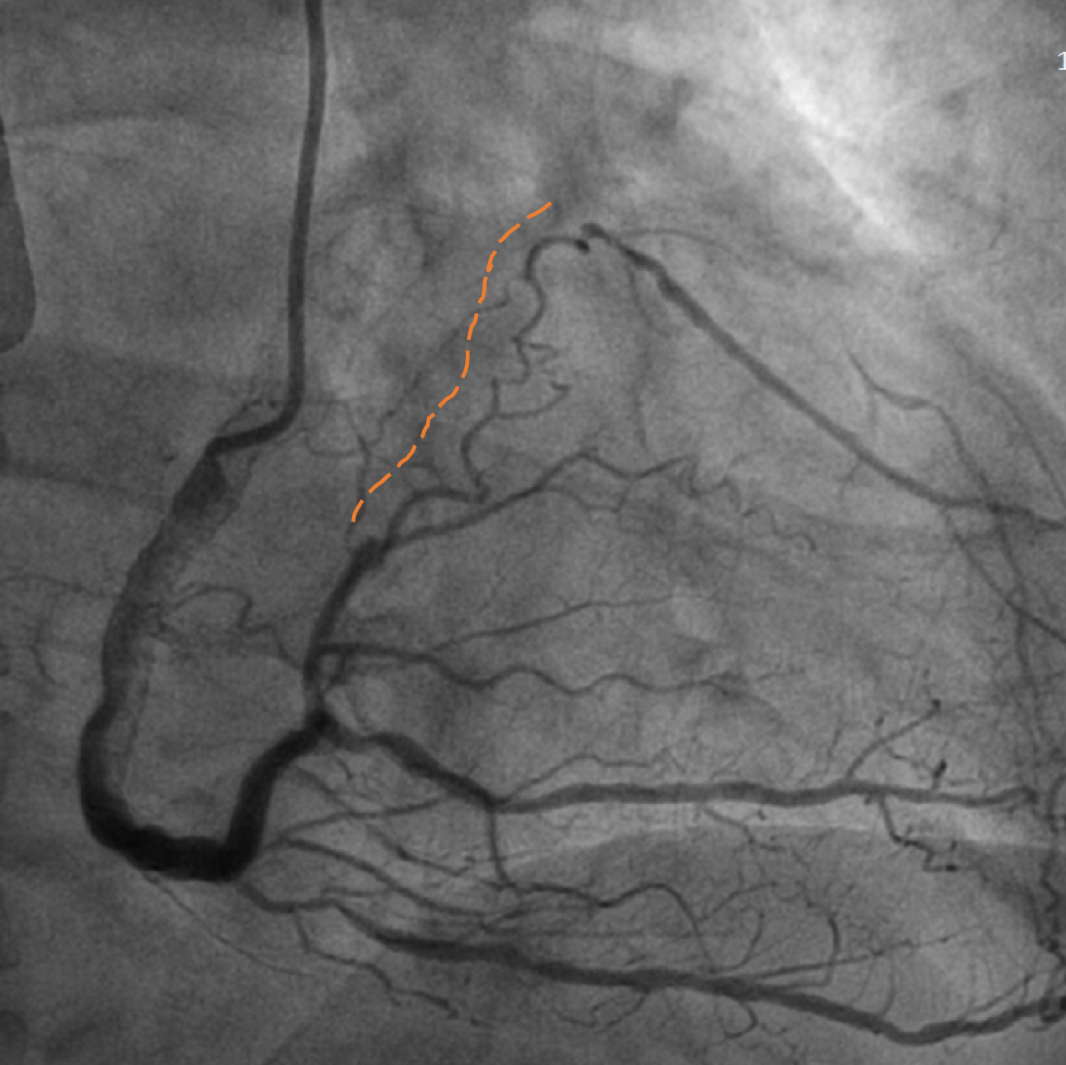

手术影像

左冠优势,LM、LCX未见狭窄,TIMI3级;LAD近段CTO,TIMI0级

RCA细小,近中段狭窄40%-50%,TIMI3级;远端可见LAD侧枝血流

策略讨论:近端纤维帽不清晰,LAD中段显影可见,闭塞段长度>20mm。间隔支逆供条件尚可。CTA提示LAD多发钙化。尝试正向开通,优选亲水性滑导丝,若失败,及时调整逆向策略。